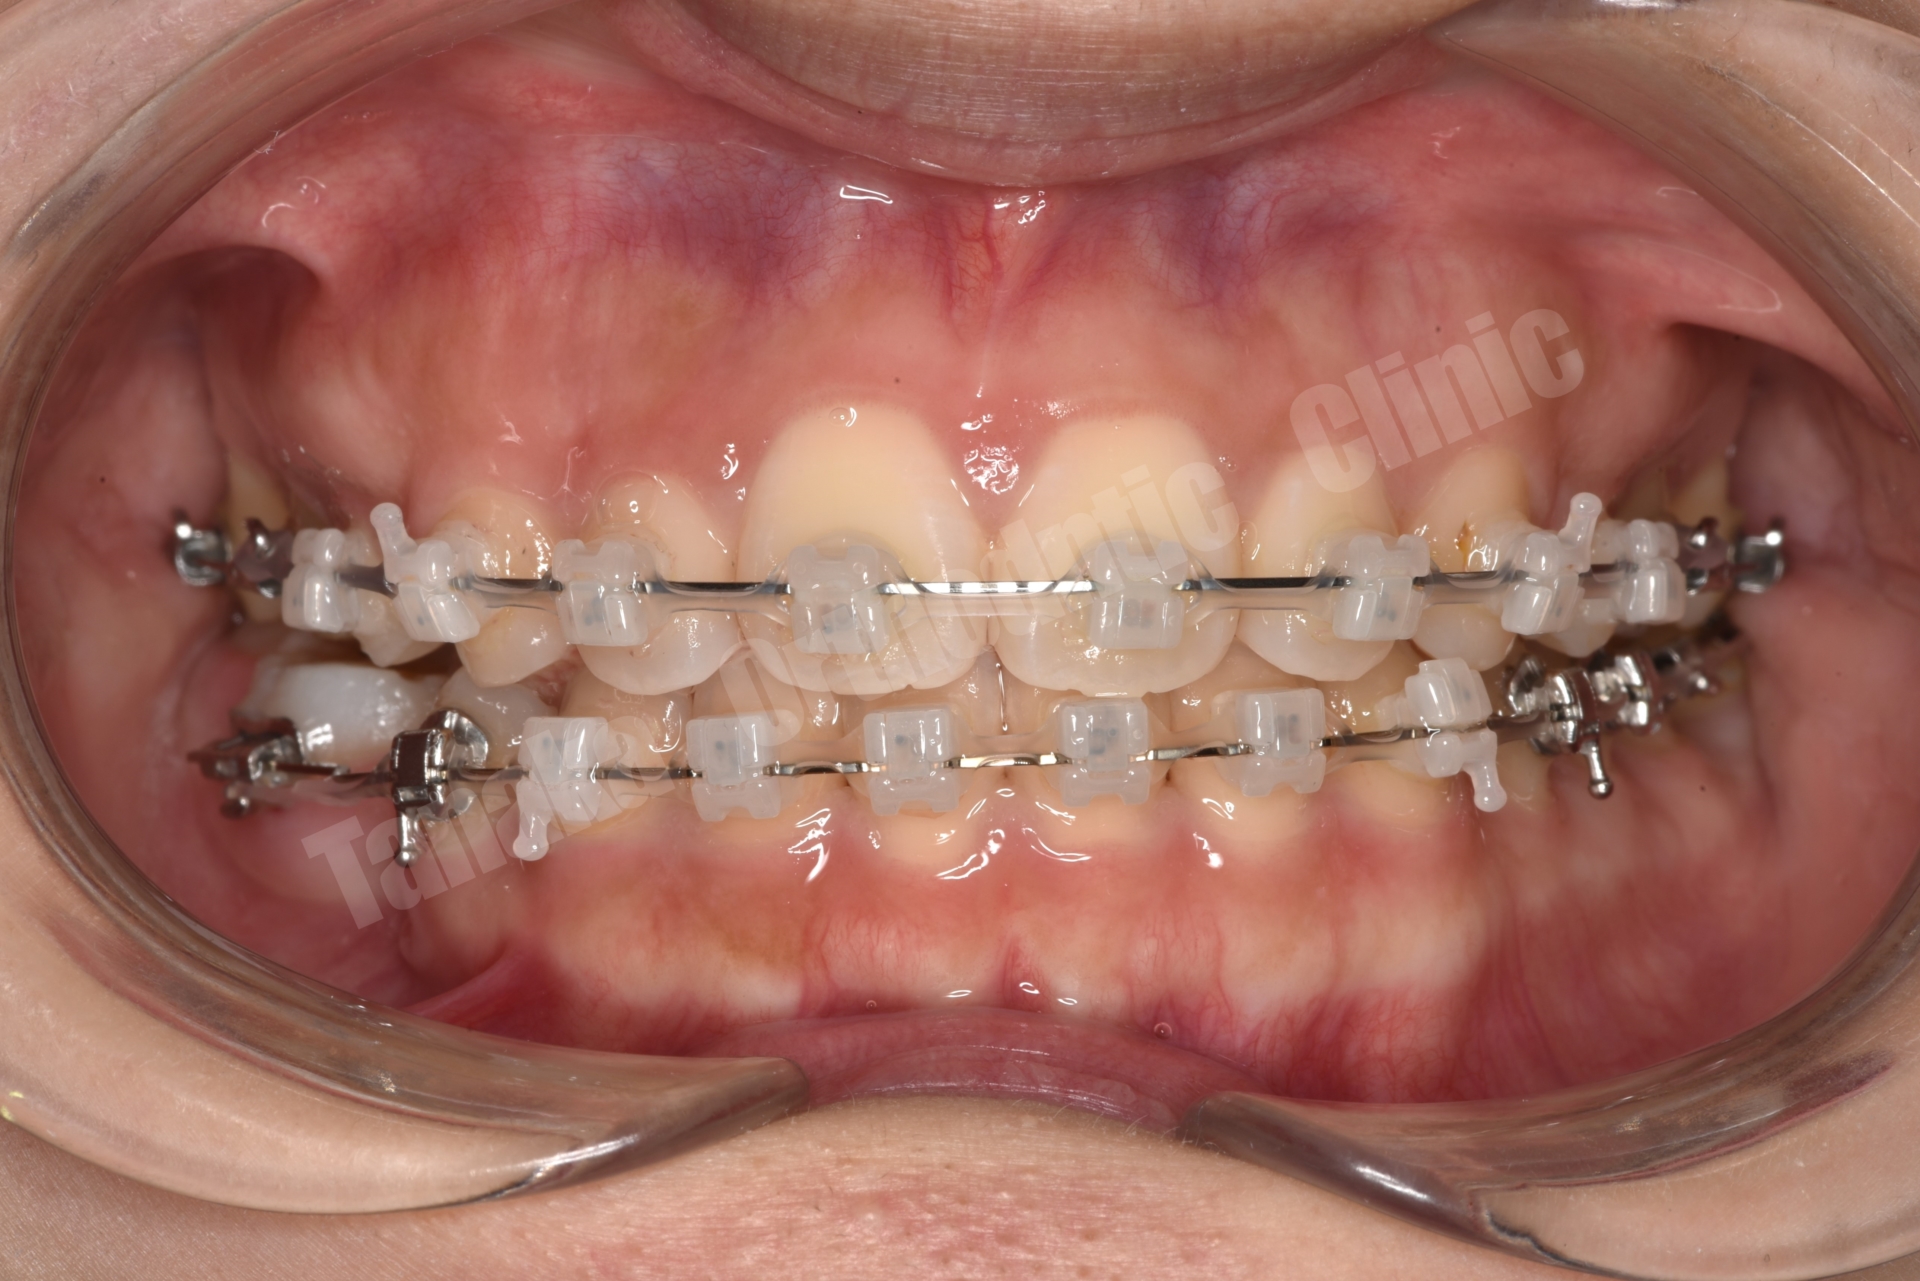

初診時の診査では、上顎前歯が唇側に傾斜しており、前歯の水平被蓋(オーバージェット)が大きい状態でした。そのため口元の突出感が認められ、前歯部は十分に噛んでいない状態でした。また下顎正中は左側へ偏位しており、右下E(乳臼歯)の残存と5番の先天欠如、さらに下顎両側7番の位置異常も確認されました。さらに患者様は10代半ばの頃に一度、非抜歯でマルチブラケット矯正を受けており、その影響もあって上顎中切歯には歯根吸収が生じ、歯根がやや短くなっている所見も認められました。

そこで治療では上下歯列に唇側マルチブラケット装置を装着し、歯列全体の排列を行いました。上顎前突を改善するため上顎両側4番を抜歯し、前歯を後退させて口元のバランスを整える計画としました。さらに下顎正中の改善のため右下Eを抜歯し、約11mmある乳臼歯部のスペース閉鎖を行う計画としました。このスペース閉鎖には矯正用アンカースクリューを使用し、右側6番・7番を近心移動させる必要があります。また治療途中で萌出してくる右下7番の位置を適切にコントロールすることも重要なポイントとなります。